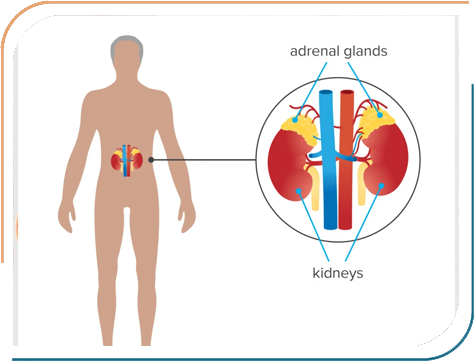

Pediatric Endocrinology is a speciality branch of Pediatrics, which deals with hormonal issues in Children and Adolescents. There are multiple endocrine glands which secrete multiple hormones required for growth, development and functioning of a child. Any disruption of deficiency of these hormones requires timely and targeted treatment by an expert- A paediatric Endocrinologist.

Dr. Jhala's expertise encompasses a wide range of paediatric endocrine disorders, including Growth abnormalities, Childhood Diabetes, Thyroid disorders in Children, Puberty-related concerns, Bone diseases and many other hormonal conditions in Children. She is dedicated to diagnosing and treating conditions such as Type 1 diabetes, Growth hormone deficiencies, and early or delayed puberty, all aimed at helping children lead healthier, more fulfilling lives. Her approach combines thorough clinical evaluation with the latest medical advancements, ensuring comprehensive care tailored to each child's needs.